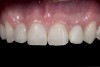

(2.) After orthodontic alignment of teeth and bleaching. Note alveolar deficiency in right lateral incisor site and diminutive left lateral incisor.

Figure 2

A 14-year-old patient presented to the office with his mother (Figure 1). His chief complaint involved the large spaces between the teeth created by his missing right maxillary lateral incisor and his small left maxillary lateral incisor. He desired to replace the missing tooth with an implant and create a beautiful smile. Upon examination, he was found to have a class I canine and molar relationship, but because he had a tooth size/arch size discrepancy and space distal to the right central incisor, the remaining incisors had drifted to the right. The left maxillary lateral incisor was peg-shaped and in a cross bite position. Studies have shown a clear association between congenitally missing teeth and reduced tooth size.59-62 Because he was only 14-years-old at the time and could not have implants placed until the cessation of growth (somewhere in the vicinity of 22 years old), he was sent to the orthodontist for alignment of the teeth.16,17 After 2 years of orthodontics, the appliances were removed, and his tooth coloration was improved using carbamide peroxide bleaching (Figure 2). Because some form of provisional needed to be placed until he was finished growing, a double-wing metal resin-bonded bridge was chosen. As discussed earlier, this is the ideal transitional prosthesis for patients that have congenitally missing maxillary lateral incisors. The benefits of this type of prosthesis include its ability to be removed and rebonded during the surgical phase of treatment and its ability to retain the roots in their proper position after orthodontic treatment.16 The final plan for the patient was to increase the width of the central and the maxillary left lateral incisor, utilizing porcelain laminate veneers to achieve the appropriate width/length ratio of 80%. A wax-up was created to idealize tooth size, a putty matrix was made from the wax-up to facilitate bonding of the incisors, and a non-precious, double-wing metal resin-bonded bridge was fabricated for lateral incisor replacement. Once the teeth were bonded to ideal size, the “Maryland Bridge” was fabricated from a polyvinyl arch impression with the newly bonded teeth (Figure 3). The metal frame was cast from a non-precious alloy to allow for fabrication of a very thin frame and to create a better surface for bonding. After sandblasting the internal aspect of the frame with CoJet™ silica (3M ESPE), accomplishing salinization, and executing cementation with a dual-cure resin cement, a fairly good adhesion to the frame was anticipated.29 The enamel surface was etched with phosphoric acid for 30 seconds, the primer (Single Bond Plus, 3M ESPE) was applied to both the internal surface of the sandblasted framework and the etched enamel, and the bridge was cemented with RelyX™ ARC (3M Espe) dual-cured resin cement (Figure 4 and Figure 5).